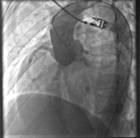

2.X線檢查

肺充血,心影擴大。逆行主動脈造影可明確顯示竇瘤破入心腔部位。